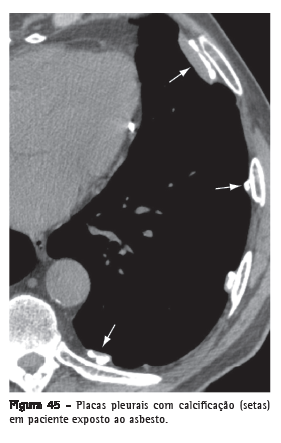

Placa pleural

Espessamento pleural focal, por vezes com calcificações, de espessura variável e com extensão de até 5 cm (Figura 45).(68) Usualmente ocorre

na superfície pleural parietal subcostal ou na pleura diafragmática.

Quando múltiplas e bilaterais, são quase sempre decorrentes de exposição ao asbesto.(69,70)